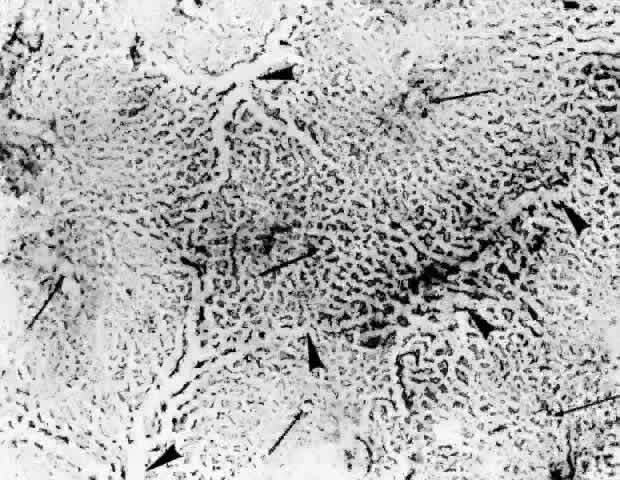

Torczynski and Tso27 reported on the architecture of the choriocapillaris in the posterior pole after examining choroidal flat preparations and transverse and oblique histologic sections (Figs. 21, 22, and 23). They described the overall appearance of the posterior choriocapillaris as a series of adjoining lobules that was striking in some preparations and subtle in others. The center of the lobule consisted of a single precapillary arteriole rimmed in a thick mantle of collagen measuring 15 to 25 μm and opening perpendicularly or curvilinearly into a capillary bed that radiated an average distance of 300 to 400 μm before changing from a radial to a circumferential direction. The circumferential capillaries in the periphery of the lobule were wider and converged from several directions, forming star-like or dendritiform configurations in the plane of the choriocapillaris. Venular openings, outward bulgings of the external choriocapillaris called atria, measured 30 to 37.5 μm and were present singly and in linear sequences underlying the circumferential capillaries. The often incomplete lobules varied in their geometric configuration, having three to six sides and ranging in area from 420 × 605 μm to 800 × 1200 μm. The lobular unit was thought to provide a preferred outflow route via the perimeter of postcapillary venules so that cross-flow from lobule to lobule would not normally occur, and thus the precapillary arteriole would function as an end-arteriole.

Fig. 21. Flat preparation of choriocapillaris, posterior pole. A. Arrowheads indicate oval openings to the postcapillary venules. The area around the precapillary arteriole (white-bordered arrow) is stained more heavily because of residual subcapillary collagen. (PAS, × 180; AFIP Neg 74-9984) B. Postcapillary venules (arrowheads) form an irregular ring bordering the capillaries that radiate from the precapillary arteriole (white-bordered arrows), thus outlining a single lobule. The capillaries are broader and clearer near the venules because of less subcapillary collagen. (PAS, × 100, AFIP Neg 74-10240) C. The openings of the postcapillary venules (as shown above) are connected with black lines; they demarcate adjoining lobules in the choriocapillaris. Capillaries from adjoining lobules enter the intervening venules. The lobules form a mosaic of adjoining vascular beds. Precapillary arterioles are indicated by white-bordered arrows. (PAS × 55; AFIP Neg 74-9985)

Fig. 22. Choriocapillaris in periphery has long, thin intercapillary septa. Arteriole in capillary plane (curved arrow). Venous anastomosis (arrowheads). (AFIP Neg 73-11415 and 12110; PAS, × 50)

Fig. 23. Prominent lobular pattern in choriocapillaris with venules (arrowheads) surrounding arterioles (arrows). (AFIP Neg 75-3895; PAS, × 55) (Torczynski E, Tso M: The architecture of the choriocapillaris at the posterior pole. Am J Ophthalmol 81:428, 1976)